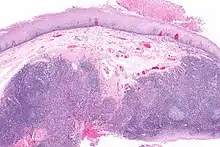

Histopathologic appearance of a poorly differentiated squamous cell carcinoma specimen. Hematoxylin-eosin stain. p16 positive, EBV negative